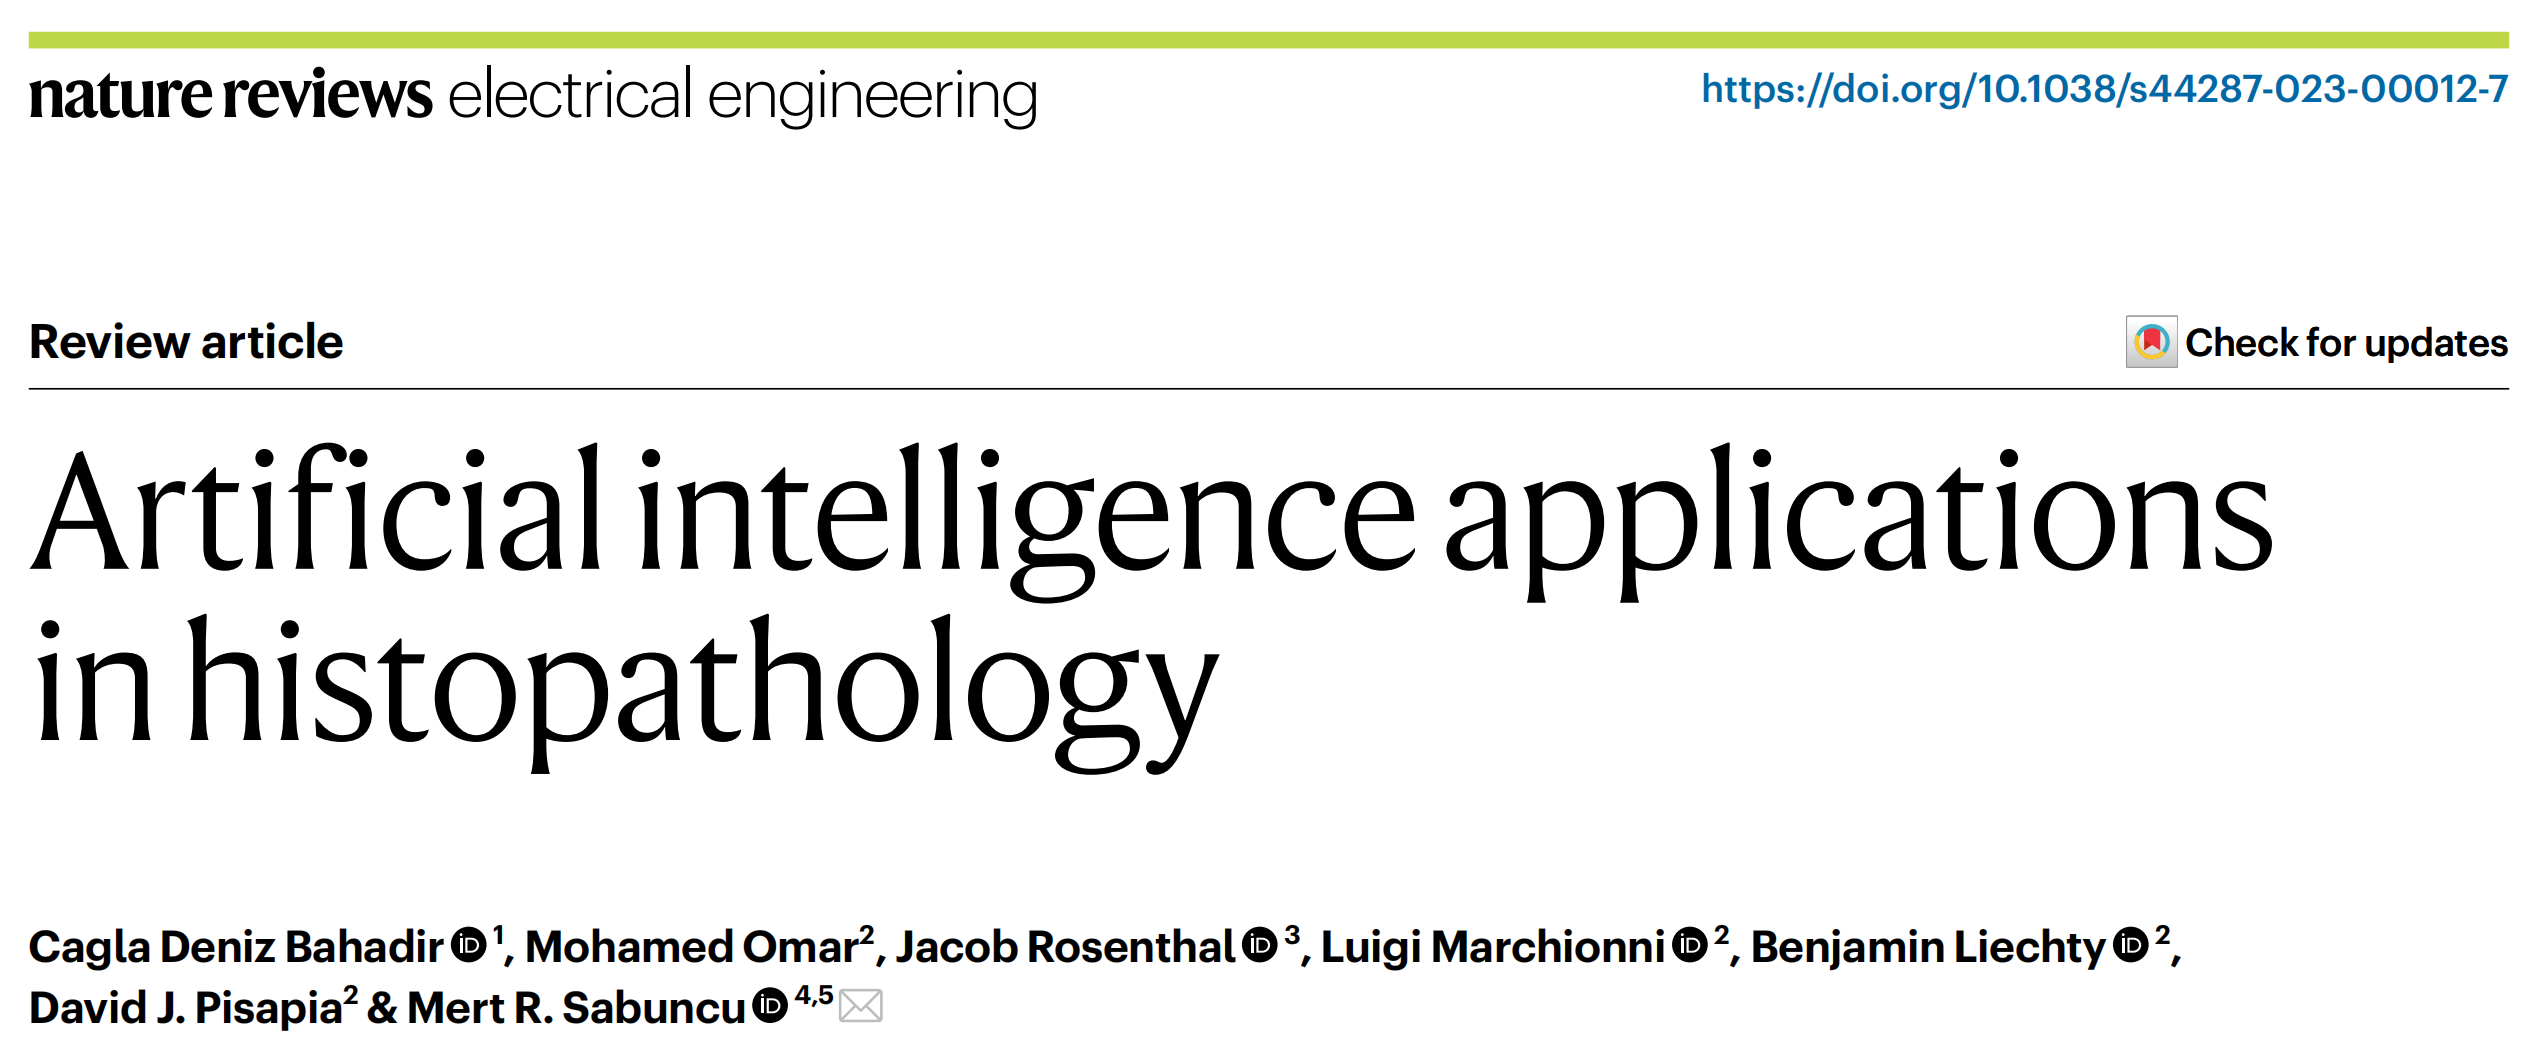

图1展示了人工智能(AI)集成的病理诊断工作流程的示意图。

图中黄色框(第一行)代表了一个典型患者的就医过程,从最初的就诊经历,通过诊断、治疗,最终到长期的治疗结果。

病理学家的核心工作流程以浅蓝色显示,其中包括手动通过显微镜检查用苏木精和伊红(H&E)染色的样本,同时结合其他辅助性的临床和分子数据(标示为“其他数据”),以得出明确的诊断。

诊断结果为进一步的临床决策制定(治疗计划)和预测任务(如预后和结果预测)提供了基础。人工智能(AI)以红色(底行)表示,有潜力增强工作流程的每一步,从工作流程优化到辅助人类病理学家的决策支持工具,再到发现新的数字生物标记物,这些生物标记物有助于优化治疗选择和预后判断。

分析:

- 患者就医过程:涉及患者从初次就诊到长期治疗结果的整个路径。

- 病理学家工作流程:包括对H&E染色样本的显微镜检查和辅助数据的综合分析,以确定最终诊断。

- 诊断的重要性:诊断是制定治疗计划和进行预后预测的基础。

- AI的辅助作用:AI技术可以在多个层面辅助病理诊断工作流程,包括:

- 工作流程优化:提高病理诊断过程的效率。

- 决策支持工具:辅助病理学家进行更准确的诊断和治疗决策。

- 数字生物标记物的发现:有助于个性化治疗和预后评估。

这个流程图强调了AI技术在病理诊断中的多功能性和潜在价值,预示着AI在医疗领域的广泛应用前景。